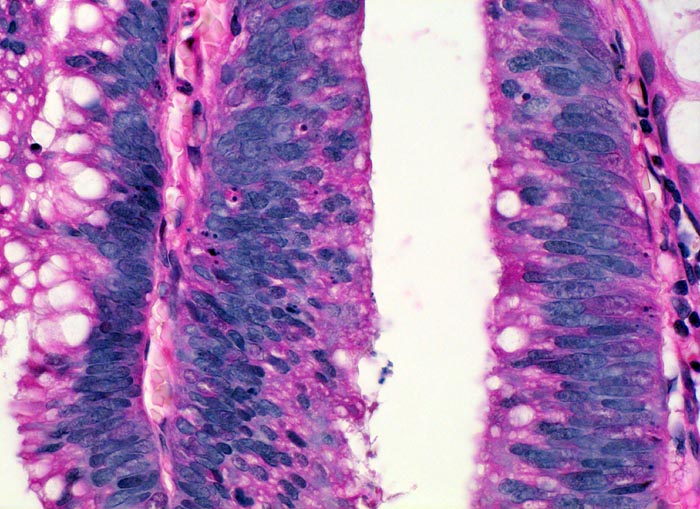

Adenom mit leichter Epitheldysplasie

Die Epithelkerne stehen sehr dicht und überlagern einander. Die Kern-Zytoplasma Relation ist zu Gunsten des leicht abgerundeten hyperchromatischen Kerns verschoben. Die Kerne sind nicht ausschliesslich basalständig, sondern wandern richtung Lumen. Die Schleimproduktion ist deutlich vermindert. Anstelle von Becherzellen finden sich lediglich kleinere intrazytoplasmatische Schleimvakuolen. Kerntrümmer von apoptotischen Zellen zeugen von einem erhöhten Zellumsatz.

Koloskopie wegen positivem Haemocculttest. Ein 5mm grosser gestielter Polyp im Colon descendens wird abgetragen.

Innerhalb eines Adenoms kann die Epitheldysplasie an verschiedenen Stellen unterschiedlich schwer ausgeprägt sein. Entscheidend für die Einteilung ist der höchste Dysplasiegrad innerhalb eines Adenoms. Aus diesem Grund und zum Ausschluss von invasiven Anteilen werden Kolonschleimhautadenome vollständig eingebettet und histologisch untersucht.